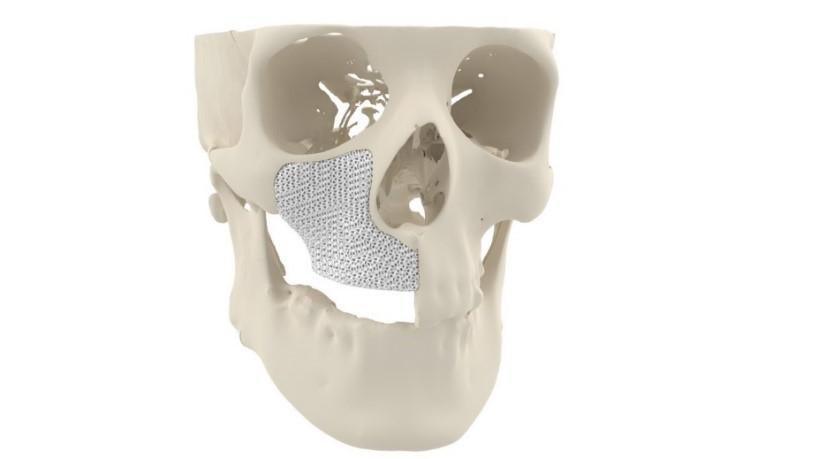

Cerhum 的 MyBone 3D 打印面部骨移植物。图片来自 Cerhum。

Cerhum(人类陶瓷)成立于 2016 年,是比利时国家科学技术研究所 Sirris 的衍生公司。该公司与列日大学合作,目标是用合成的 3D 打印替代物替代自体移植物――取自患者身体其他部位的骨骼。迄今为止,该公司已经 3D 打印了数以万计的合成骨移植物,已被一系列公司用于骨科植入物。MyBone 是一种针对患者的 3D 打印骨移植物,旨在治疗患有严重面部畸形的患者。移植物由羟基磷灰石制成,磷酸钙是天然骨骼的主要矿物质成分,3D 打印具有独特的多孔结构以促进骨骼生长。

“我们的 3D 打印骨植入物提供了一种独特的专利多孔结构,允许血管向内生长,”Nolens 说。 “这个过程称为血管化,是成功实现骨向内生长的关键。因此,MyBone 的骨向内生长速度比目前可用的骨移植颗粒快 7 倍。”MyBone 现在已根据医疗器械法规 2017/745 验证可用于欧洲患者,并已在比利时主管当局注册。骨移植物也通过了 ISO 13485 认证,因此现在可供外科医生用作颌面手术的患者专用植入物。作为两年前控制释放阶段的一部分,一名患者接受了 MyBone 移植植入物,据报道,根据最近的 CT 扫描,该植入物现在看起来与天然骨骼完全一样。

Cerhum 的 MyBone 3D 打印面部骨移植物。图片来自 Cerhum。

Cerhum(人类陶瓷)成立于 2016 年,是比利时国家科学技术研究所 Sirris 的衍生公司。该公司与列日大学合作,目标是用合成的 3D 打印替代物替代自体移植物――取自患者身体其他部位的骨骼。迄今为止,该公司已经 3D 打印了数以万计的合成骨移植物,已被一系列公司用于骨科植入物。MyBone 是一种针对患者的 3D 打印骨移植物,旨在治疗患有严重面部畸形的患者。移植物由羟基磷灰石制成,磷酸钙是天然骨骼的主要矿物质成分,3D 打印具有独特的多孔结构以促进骨骼生长。

“我们的 3D 打印骨植入物提供了一种独特的专利多孔结构,允许血管向内生长,”Nolens 说。 “这个过程称为血管化,是成功实现骨向内生长的关键。因此,MyBone 的骨向内生长速度比目前可用的骨移植颗粒快 7 倍。”MyBone 现在已根据医疗器械法规 2017/745 验证可用于欧洲患者,并已在比利时主管当局注册。骨移植物也通过了 ISO 13485 认证,因此现在可供外科医生用作颌面手术的患者专用植入物。作为两年前控制释放阶段的一部分,一名患者接受了 MyBone 移植植入物,据报道,根据最近的 CT 扫描,该植入物现在看起来与天然骨骼完全一样。